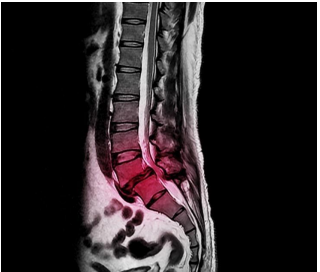

One morning, as this patient was on his stroll, his right leg began to give out, and he was unable to return home on his own. After he called his wife to pick him up, he immediately called our office for an appointment. We sent him for a magnetic resonance image (MRI) of his lower back. The results revealed a herniated L5 disc; it was touching his spinal nerves with 1 mm of space to spare. He was immediately referred to a neurosurgeon for a consultation to discuss lower back surgery. This patient was diagnosed with cauda equina syndrome (CES).

A medical emergency can result depending on the severity of these symptoms. People experiencing any of these symptoms should seek a consultation with a neurologist or neurosurgeon for an assessment that requires a magnetic resonance image (MRI) of the lumbar spine and a myelogram to assess damage to the spinal cord.

NIH. (2020). Cauda Equina Syndrome. https://rarediseases.info.nih.gov/diseases/10987/cauda-equina-syndromeYok_onepiece. (2020). [MRI Image]. A lateral projection of lumbar spine x-ray showing degenerative

spondylolisthesis at L5/S1 level that causes low back pain and sciatica.

https://www.shutterstock.com/image-photo/lateral-projection-lumbar-spine-xray-showing-1774387022